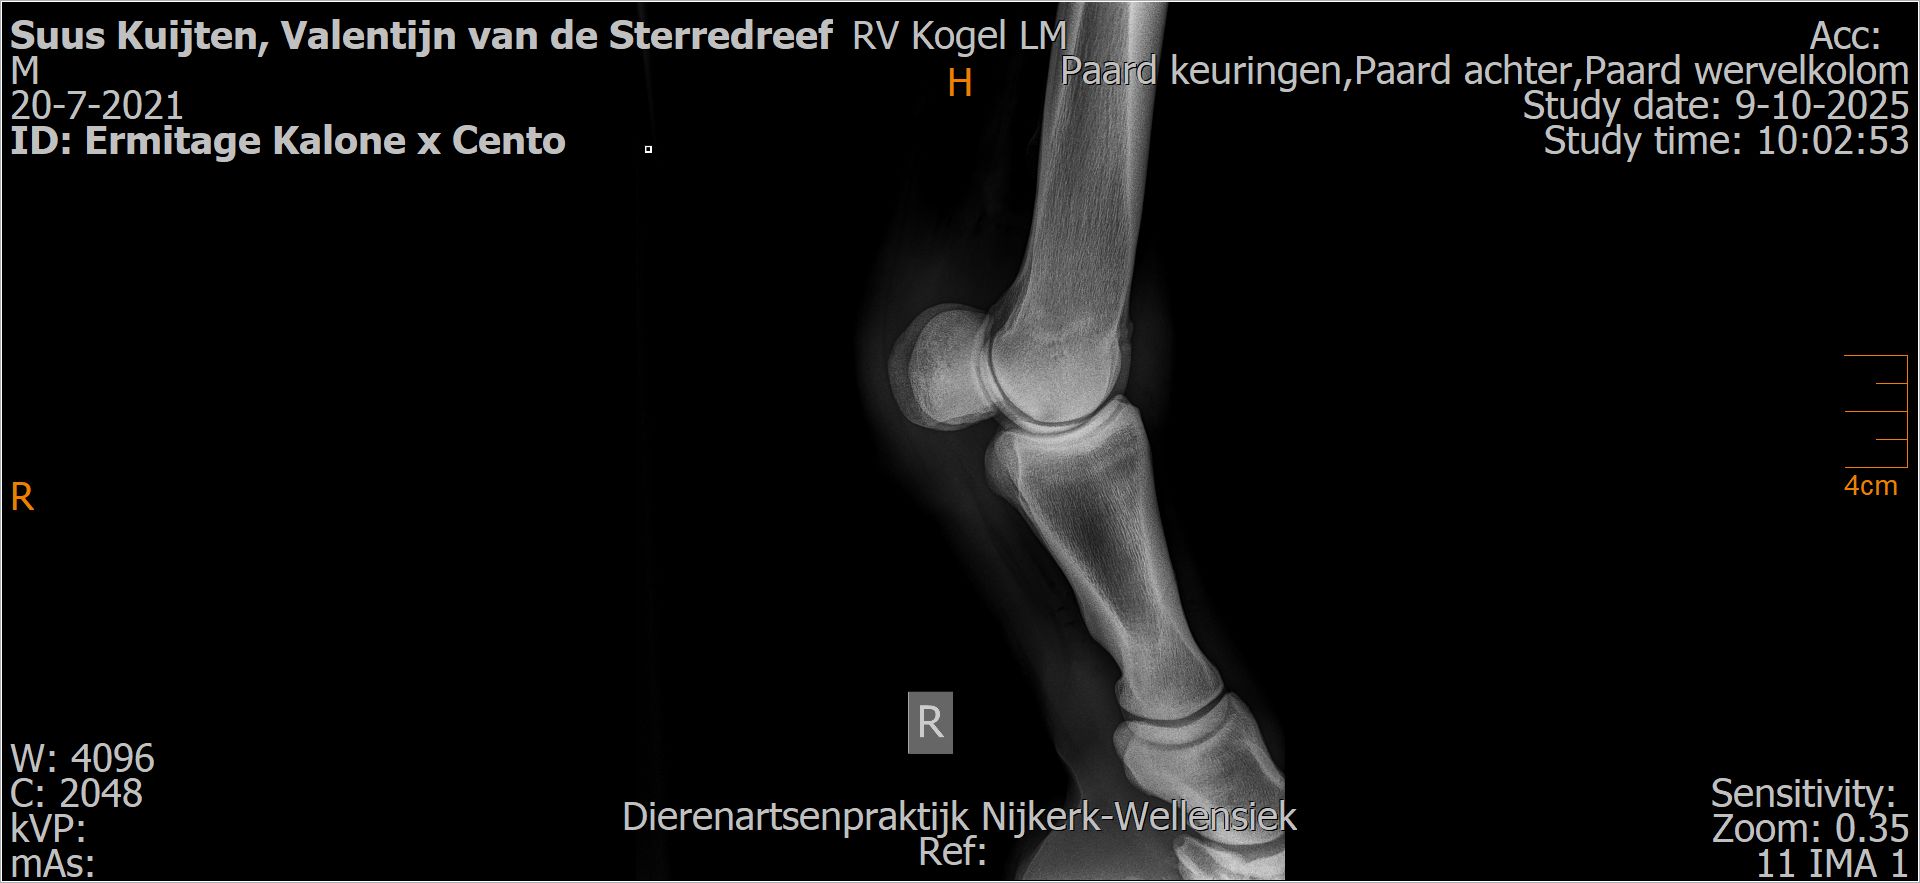

Valentijn van de Sterredreef

Röntgenfoto’s